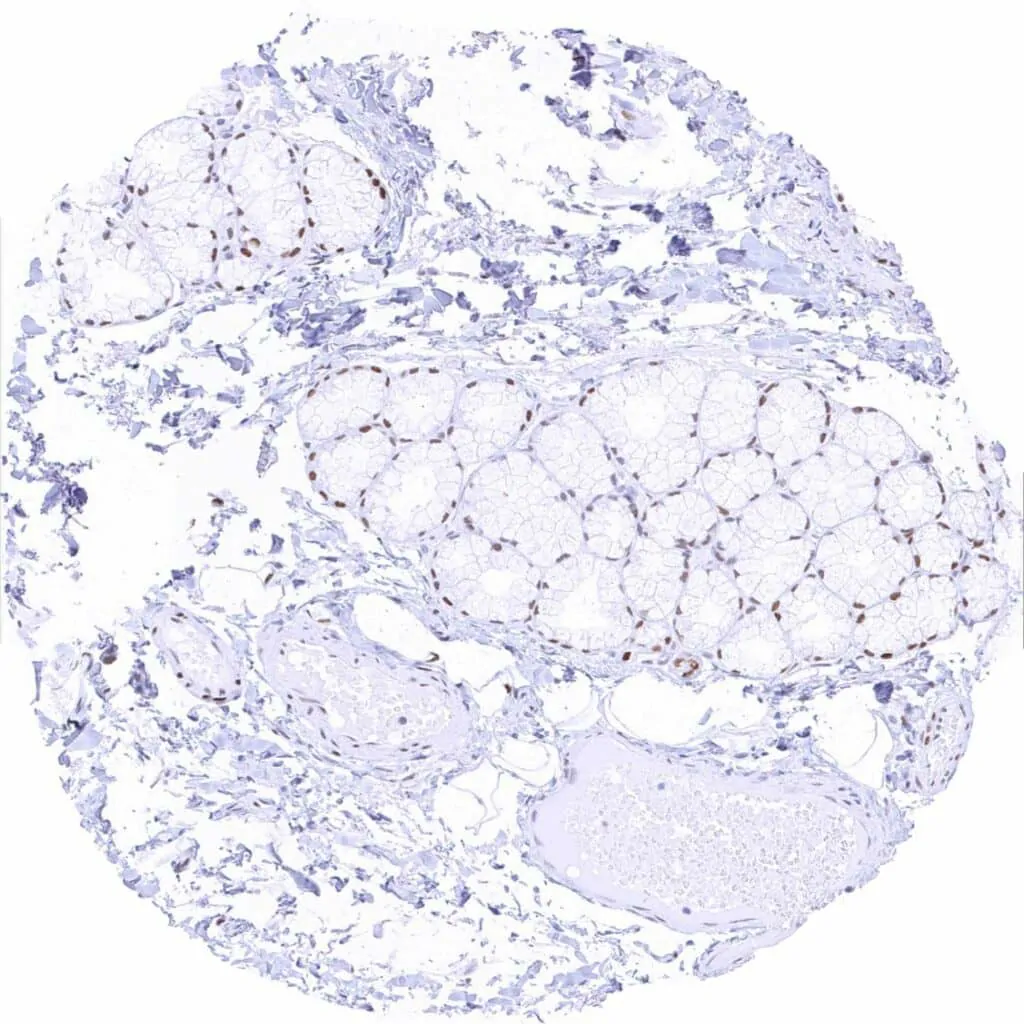

Fat